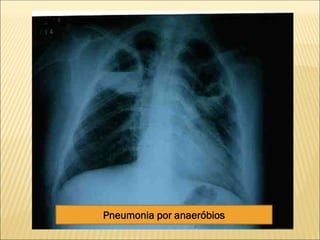

PNEUMONIA SEGMENTAR

Pneumonia por anaeróbios